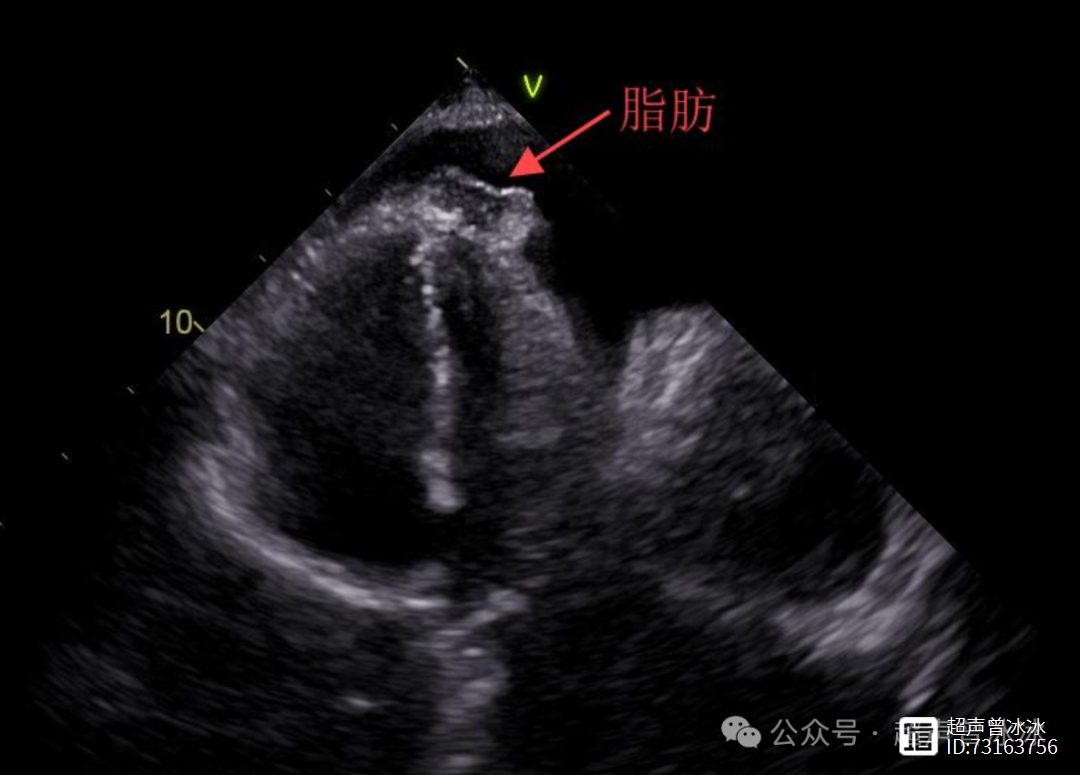

4、少量心包积液本身通常不严重,但需结合病因和症状综合判断,其严重性主要取决于积液原因及是否引发并发症具体分析如下一少量心包积液的定义与影响定义少量心包积液指心包腔内液体量较少具体数值因诊断标准而异,通常通过超声心动图评估,未对心脏功能产生明显压迫对心脏功能的影响少量积液不。

10、1 积液量本身的影响少量心包积液通常指心包腔内液体量为50150ml尽管量较少,但若液体积聚速度较快或位置特殊,可能压迫心脏,影响其舒张功能,导致心脏输出量减少例如,短期内迅速增加的少量积液可能比慢性积聚的等量积液更危险2 病因是关键决定因素不同病因导致的心包积液严重性差异显著感染。